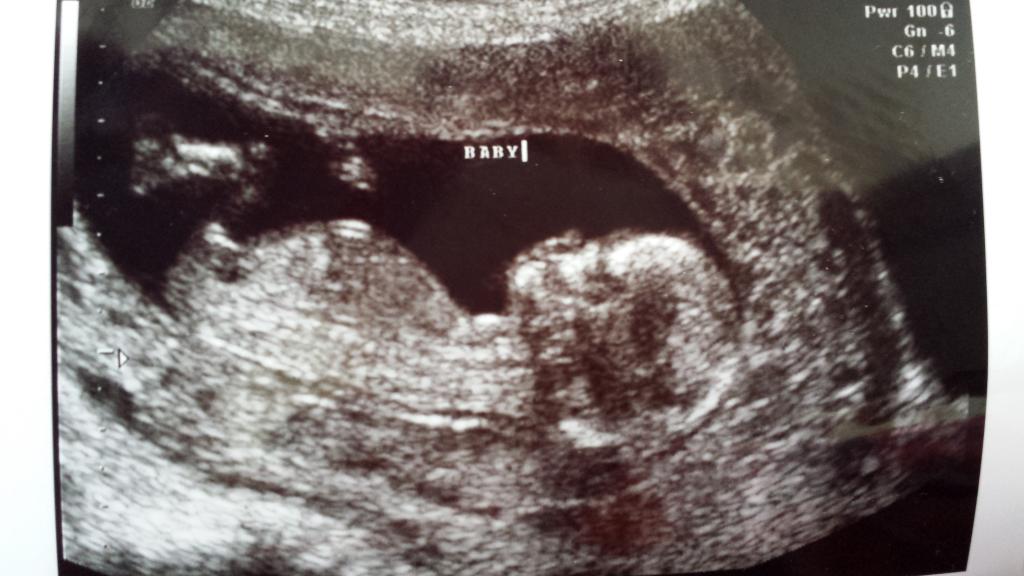

13 weeks:

I'd guess boy for this one, even though the angle is more straight. But what's the gestation? Could be a girl, if later.

13 weeks, thanks for looking!

I am guessing girl. At 13 weeks I would expect a boy nub to be at a much greater angle.

im gonna say boy because of the shape (bump on end)

We have 3 boys and lost a girl at 20 weeks this past summer. Looking back, while this nub looks flatish to me, my girl's nub was pointing down and very forked, it was a very obvious girl nub. This one looks really different. I'm sad, but I have to say, hearing a lot of boy guesses prior to finding out Dec. 23rd makes me get more prepared that it likely is another boy. Focused on health more than anything. Thank you all for your guesses! I'll update when we know.

I guess girl...purely because at 13 weeks I would have though the nub would be a lot more angled...I'm no expert though! good luck :)